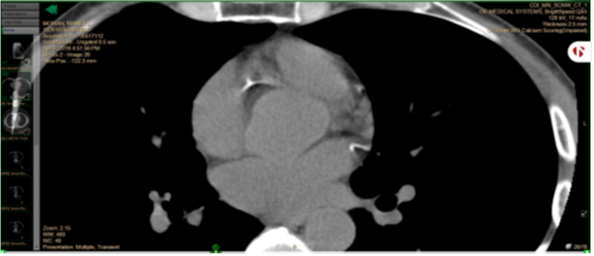

No cardiac events happened during the study period. The right coronary artery calcium score dropped from 39 in 2019 to 21 in 2020. Circumflex calcium score dropped from 9 to 2. In the CT images below, left upper cardiac artery is the right coronary artery; right lower artery is the circumflex.